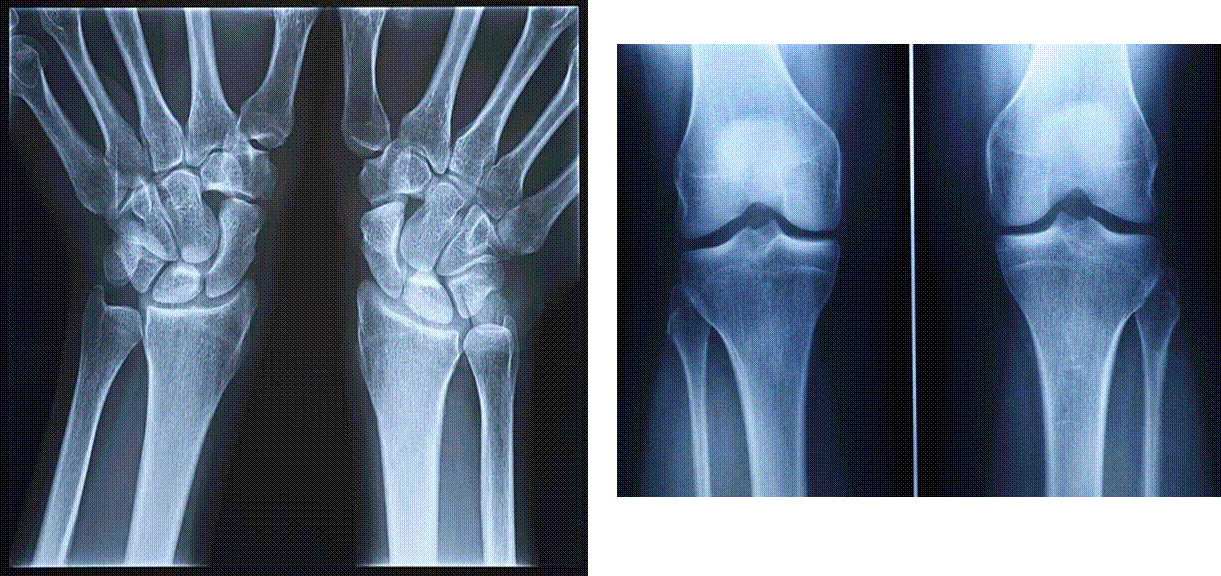

Простой сустав – это сустав, в образовании которого принимают участие только две суставные поверхности, каждая из которых может быть образована одной или несколькими костями. Например, суставные поверхности межфаланговых суставов образованы только двумя костями; а в лучезапястном суставе три кости проксимального ряда запястья образуют единую суставную поверхность.